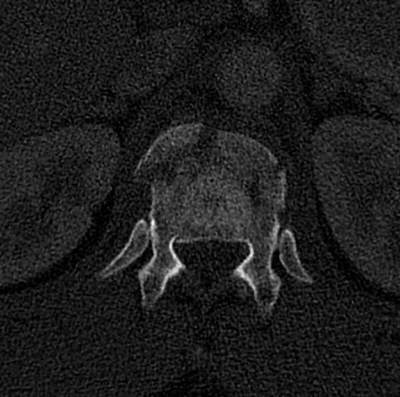

A 36 y/o restrained driver presented after an MVC. He complained of weakness and a numb feeling in his legs. Examination showed 4-/5 strength in his proximal and 3/5 strength in his distal lower extremities and an L1 sensory level. Lumbar spine radiographs and axial CT through the level of injury are shown below. What is the spinal injury type:

Answer

• Compression fracture

• Burst fracture

• Teardrop fracture

• Fracture dislocation

• Chance fracture